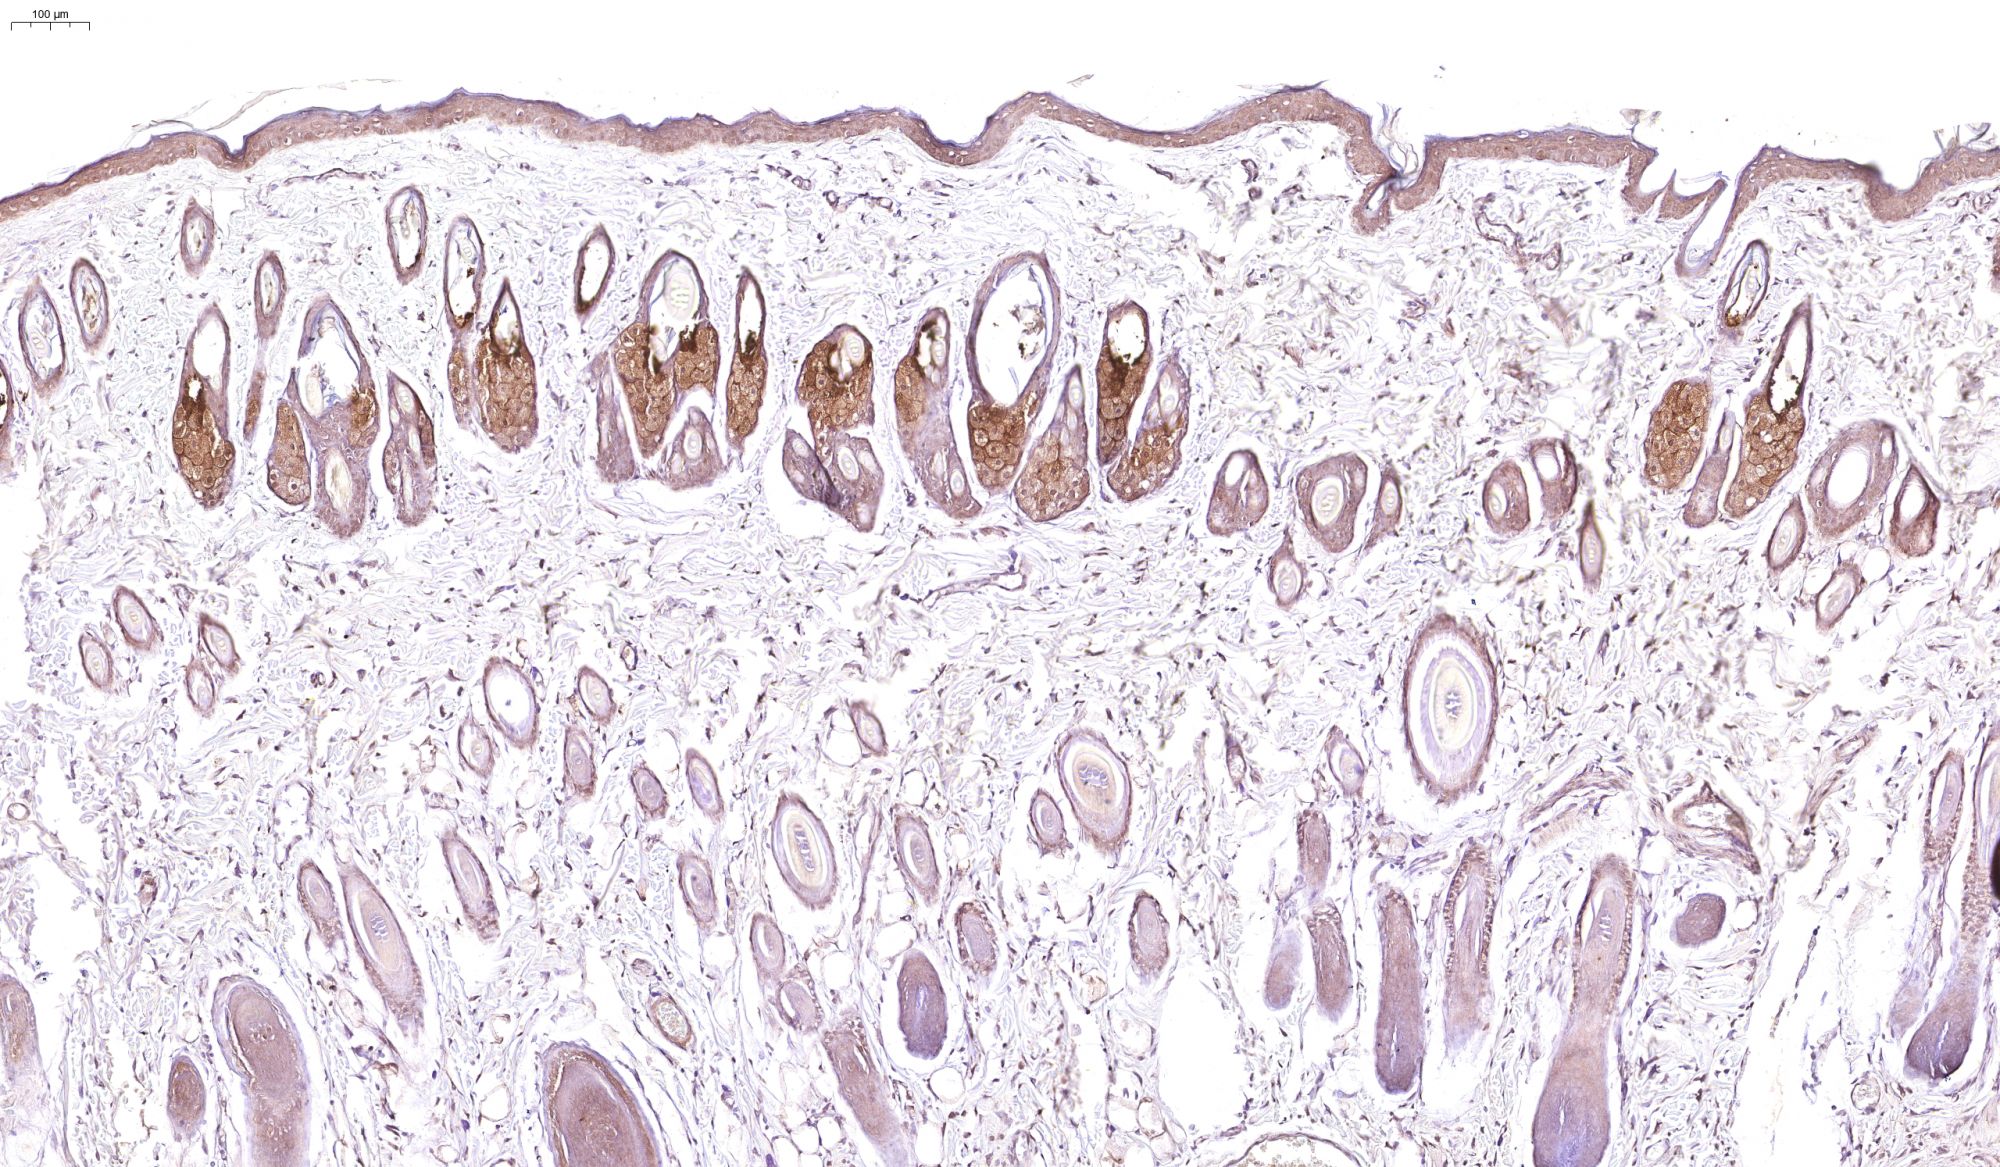

優(yōu)秀案例(免疫組化)